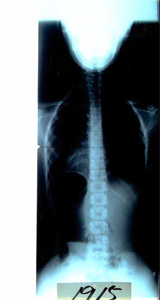

母親より送られてきたレントゲンとお手紙です。

結果 真っ直ぐ。どこの病院へ行かれてもよいですとご返事しました。

レントゲン写真   お手紙